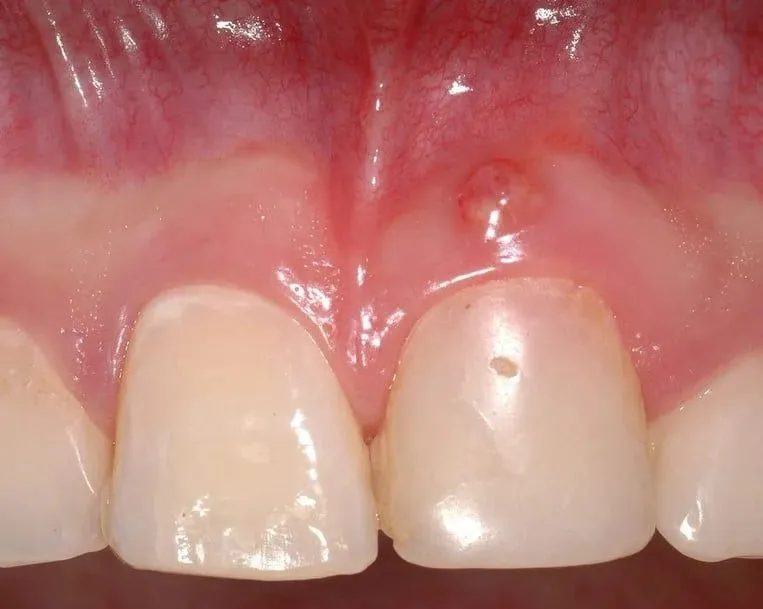

Jak wygląda afta na dziąśle? Przykłady zdjęć dla identyfikacji

Afty na dziąśle mają charakterystyczny wygląd, co ułatwia ich identyfikację. W przypadku afty można zauważyć czerwoną obwódkę oraz centralny nalot, który może być biały lub żółty. Warto zwrócić uwagę na te cechy, aby odróżnić afty od innych zmian w jamie ustnej, takich jak opryszczka czy pleśniawki. Poniżej znajduje się tabela, która porównuje symptomy afty z innymi powszechnymi zmianami w jamie ustnej.| Rodzaj zmiany | Cechy charakterystyczne |

| Afta | Czerwona obwódka, białawy lub żółtawy nalot |